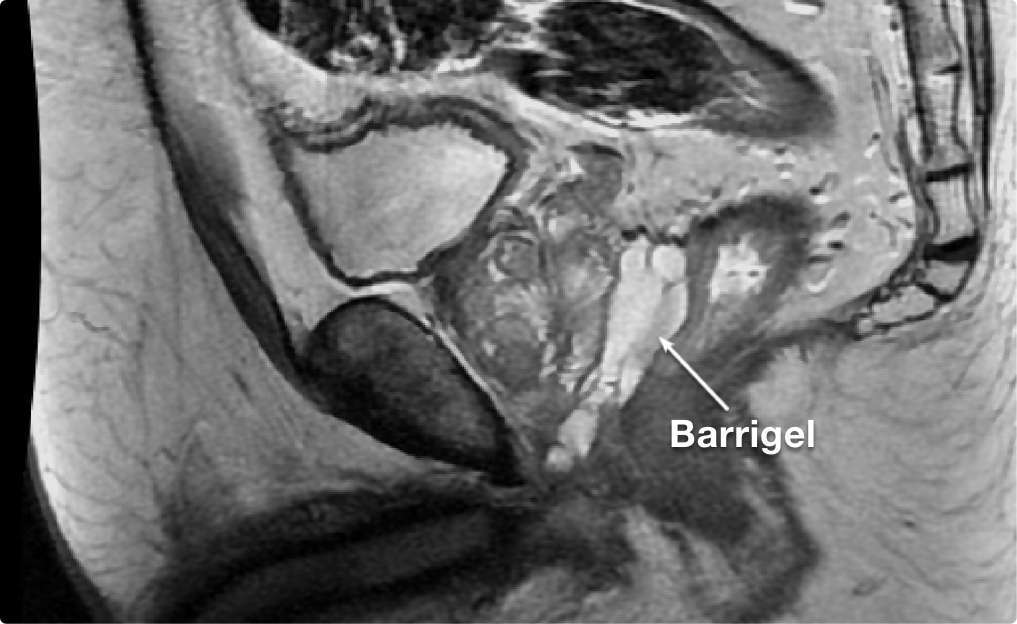

Barrigel は、対照群と比較してグレード2 以上の急性期消化管毒性を

低減することが証明

されている唯一の直腸スペーサーあり、副作用

の減少をもたらします1

BarrigelのPivotal試験において Barrigelと関連した有害事象は

0件でした1